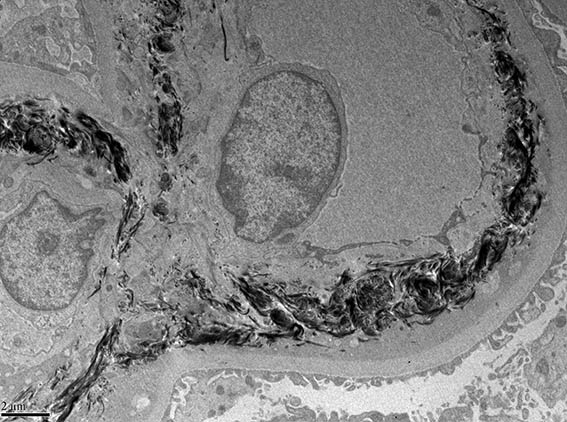

A 33-year-old man presented with pedal edema, persistent proteinuria and hypertension. Her past and family histories were unremarkable. Her blood pressure was 160/100 mm Hg. Physical examination revealed pedal and facial edema, without other alterations. Laboratory tests showed proteinuria of 4.7g/24 h, serum creatinine 1,0 mg/dL, microhematuria, normal serum complement levels, ANA negative; HIV, hepatitis B and C viral infections were negative. Ultrasound of the abdomen showed normal sized kidneys.

Kidney biopsy was performed. Look at the images.

Figure 7. Electron microscopy, original magnification, X6,000.